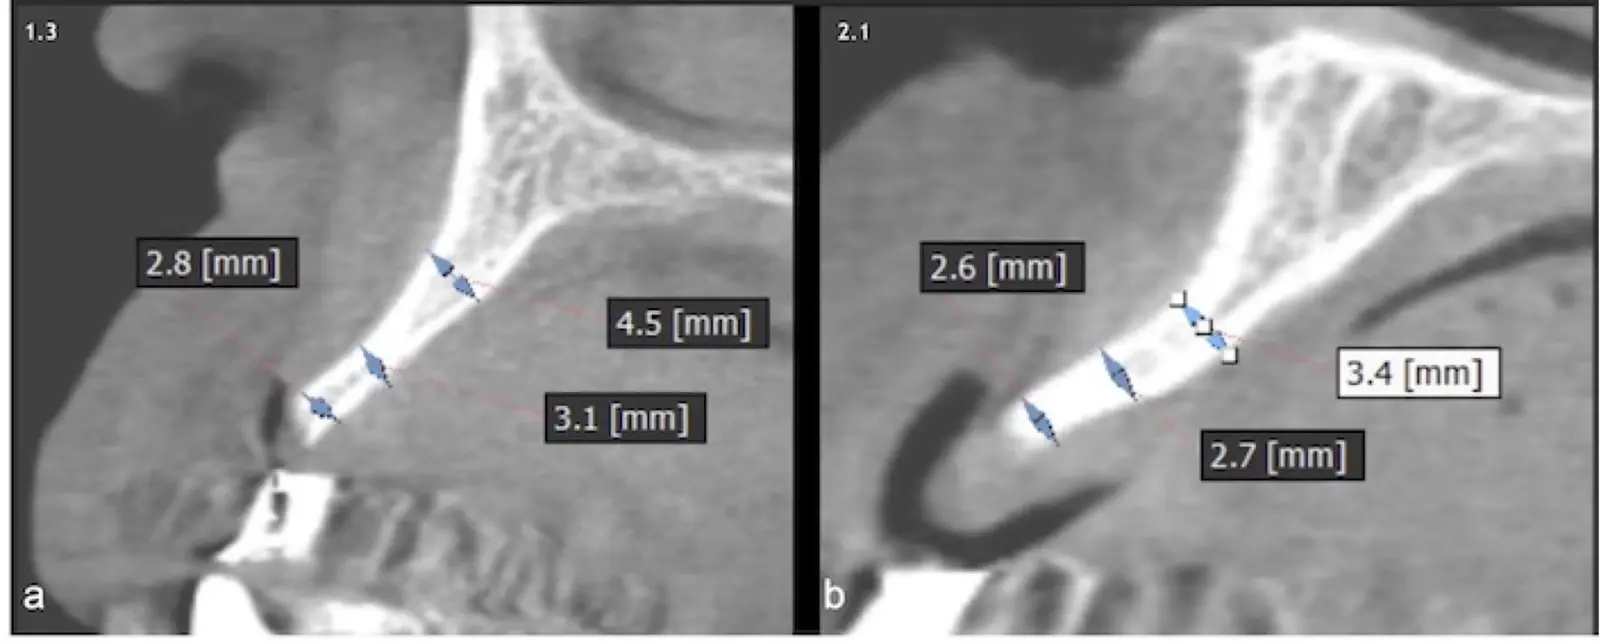

Paciente de sexo femenino de 53 años llega a la consulta solicitando una prótesis implantosoportada. En la evaluación clínica se observa un edentulismo total superior con una severa reabsorción ósea generalizada, a excepción de la pieza 2.3, que se encontraba en estado de remanente radicular. En la evaluación tomográfica se corrobora el hallazgo clínico y se indica una reconstrucción de reborde con injertos en bloque previo a la planificación de implantes dentales.

Figura 18. Vista clínica en la que se evidencia la deficiencia horizontal severa del reborde alveolar.

Figura 19. Tomografía computarizada de la zona receptora. Pieza 1.3 (a). Pieza 2.1 (b).